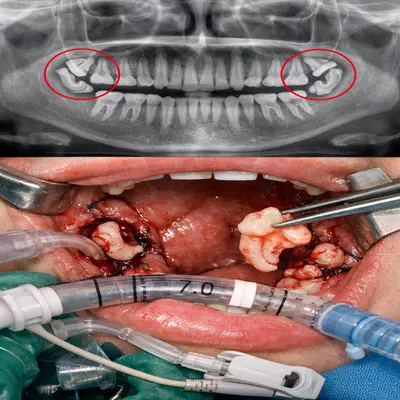

در شرایط خاص، بله؛ برخی بیماران یا جراحیهای پیچیده ممکن است به بیهوشی عمومی (در بیمارستان با لولهگذاری و تنفس با دستگاه) نیاز داشته باشند.

بیهوشی عمومی حین جراحی دندان عقل با لولهگذاری و پایش علائم حیاتی

بیهوشی عمومی کمکاربرد است، چون نیاز به بیمارستان، لولهگذاری و کنترل تنفس با دستگاه دارد. این روش فقط در شرایط خاص انجام میشود؛ مثل جراحیهای بسیار پیچیده، بیماران با شرایط پزشکی ویژه یا زمانی که انجام جراحی در کلینیک امکانپذیر نیست. به همین دلیل، برای اغلب بیماران گزینهٔ اول محسوب نمیشود.

محیط انجام:

بیهوشی عمومی فقط در بیمارستان انجام میشود؛ اما سدیشن (آرامبخشی/خواب مصنوعی) در کلینیک و با حضور متخصص بیهوشی قابل انجام است. -

کنترل تنفس:

در بیهوشی عمومی تنفس بیمار بر عهدهٔ دستگاه است و لولهگذاری انجام میشود. در سدیشن بیمار خودش نفس میکشد و فقط در خواب عمیق و آرام قرار دارد. -